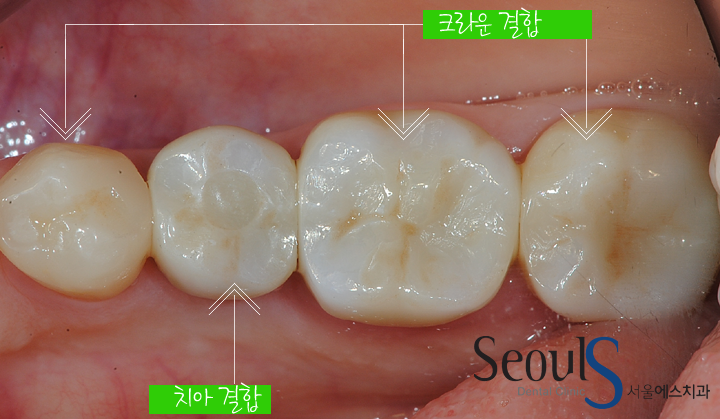

임시치아 과정을 거쳐

최종 보철물과 지르코니아 크라운을 결합한 모습입니다

서울에스치과는 CAD/CAM 장비로 보철물을 제작합니다

캐드캠은 풀어서 쓰면 Computer Aided Design/ Computer Aided Manufacturing입니다.

컴퓨터를 이용해 보철물을 설계하고 지르코니아나 티타늄 블록을 깎아서

임플란트보철물, 지르코니아크라운, 인레이 등을 정확하게 만드는 방법입니다

CAD/CAM 보철물은

우수한 강도의 블록을 컴퓨터가 정밀하게 깎아서 만들기 때문에

완성된 보철물은 강도가 강하고 표면 활택도가 매우 좋아서

깨지거나 시간이 지나도 치태가 끼는 문제는 거의 없습니다

서울에스치과는 CAD/CAM 장비로

임플란트 보철물, 지르코니아크라운, 인레이 등을 제작하고 있습니다